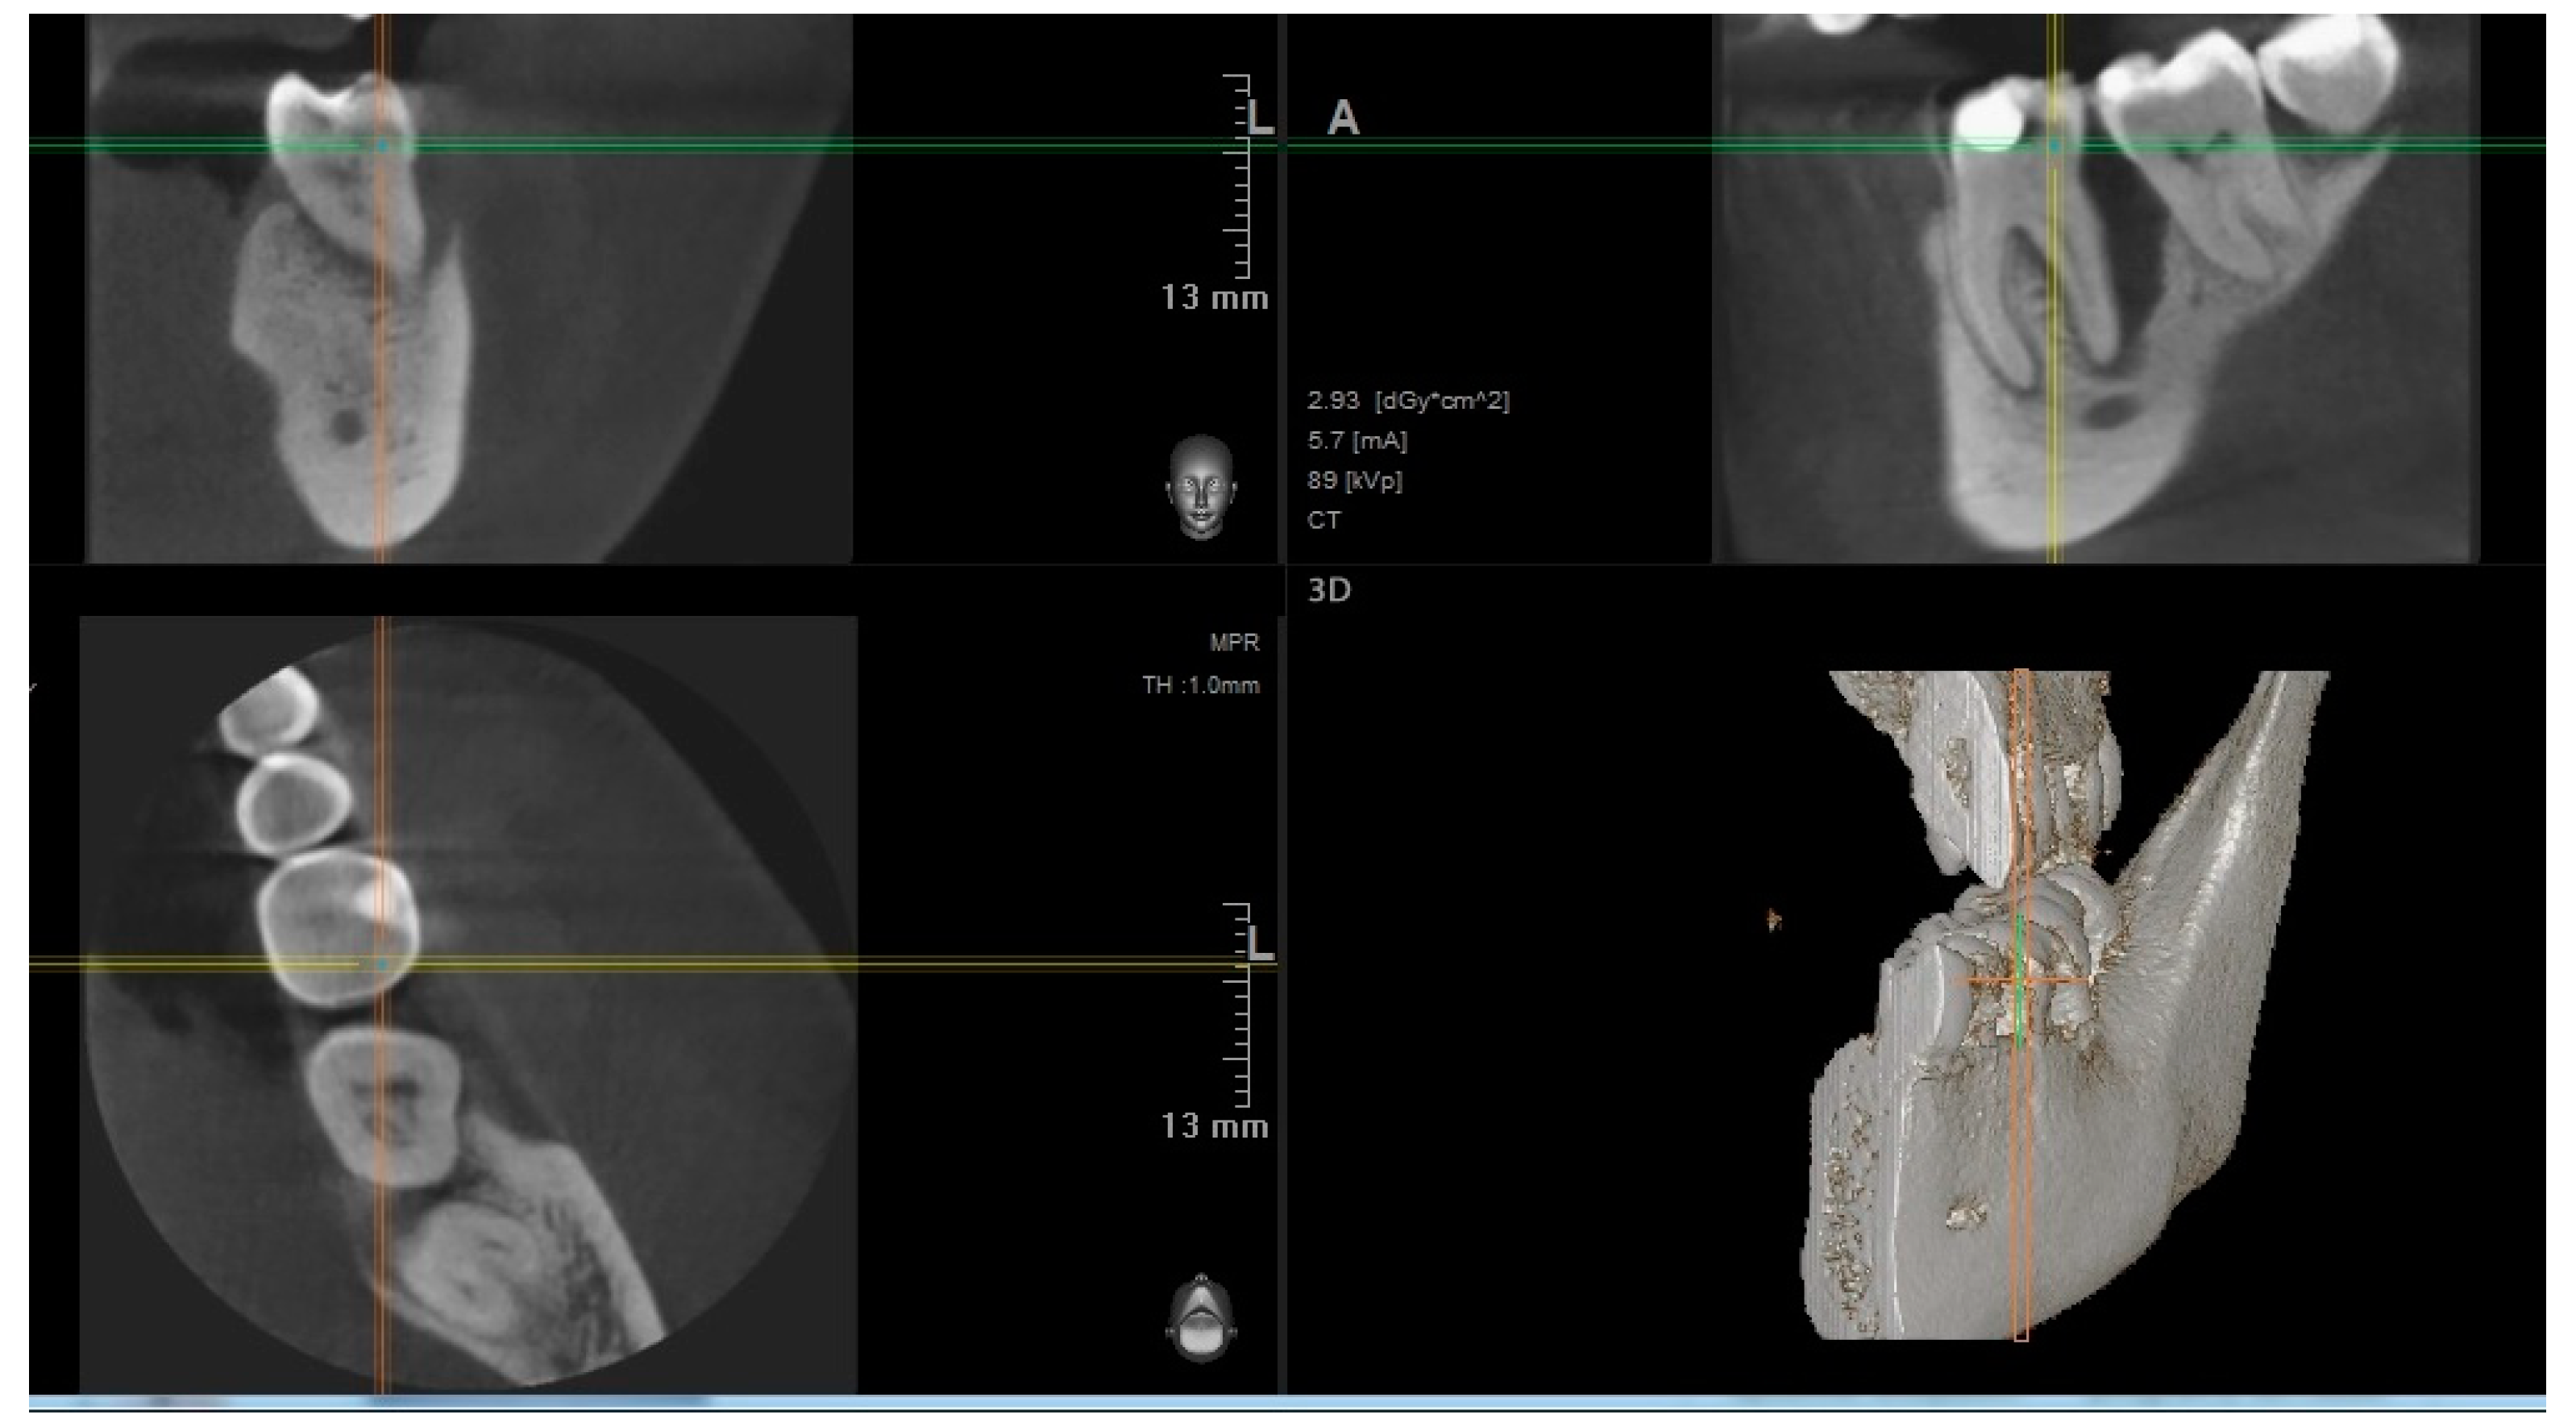

| Number of Tooth | 36 | 36 | 37 | 36 | 36 | 27 | Average Volume B/A (mm³) |

| Volume before treatment (mm³) | 654.4 | 650 | 498 | 300 | 220 | 205 | |

| Volume after treatment (mm³) | 309 | 260 | 220 | 140 | 110 | 115 | 421.23/192.3 |

| Change in percent (%) | 52.8 | 60 | 65 | 53 | 50 | 44 |

| Number of Tooth | 46 | 47 | 36 | 37 | 16 | 27 | Average Volume B/A (mm³) |

| Volume before treatment (mm³) | 287.3 | 450 | 650 | 700 | 300 | 520 | |

| Volume after treatment (mm³) | 207.1 | 310 | 400 | 580 | 245 | 360 | 484.55/350.4 |

| Change in percent (%) | 28 | 31 | 38 | 17 | 18 | 30.7 |

| Group | Amount of Teeth | Average | SD | ST p | M-W p |

|---|---|---|---|---|---|

| 1 | 6 | 192.3 | 83.0 | ||

| 2 | 6 | 350.4 | 133.1 | 0.033 | 0.037 |